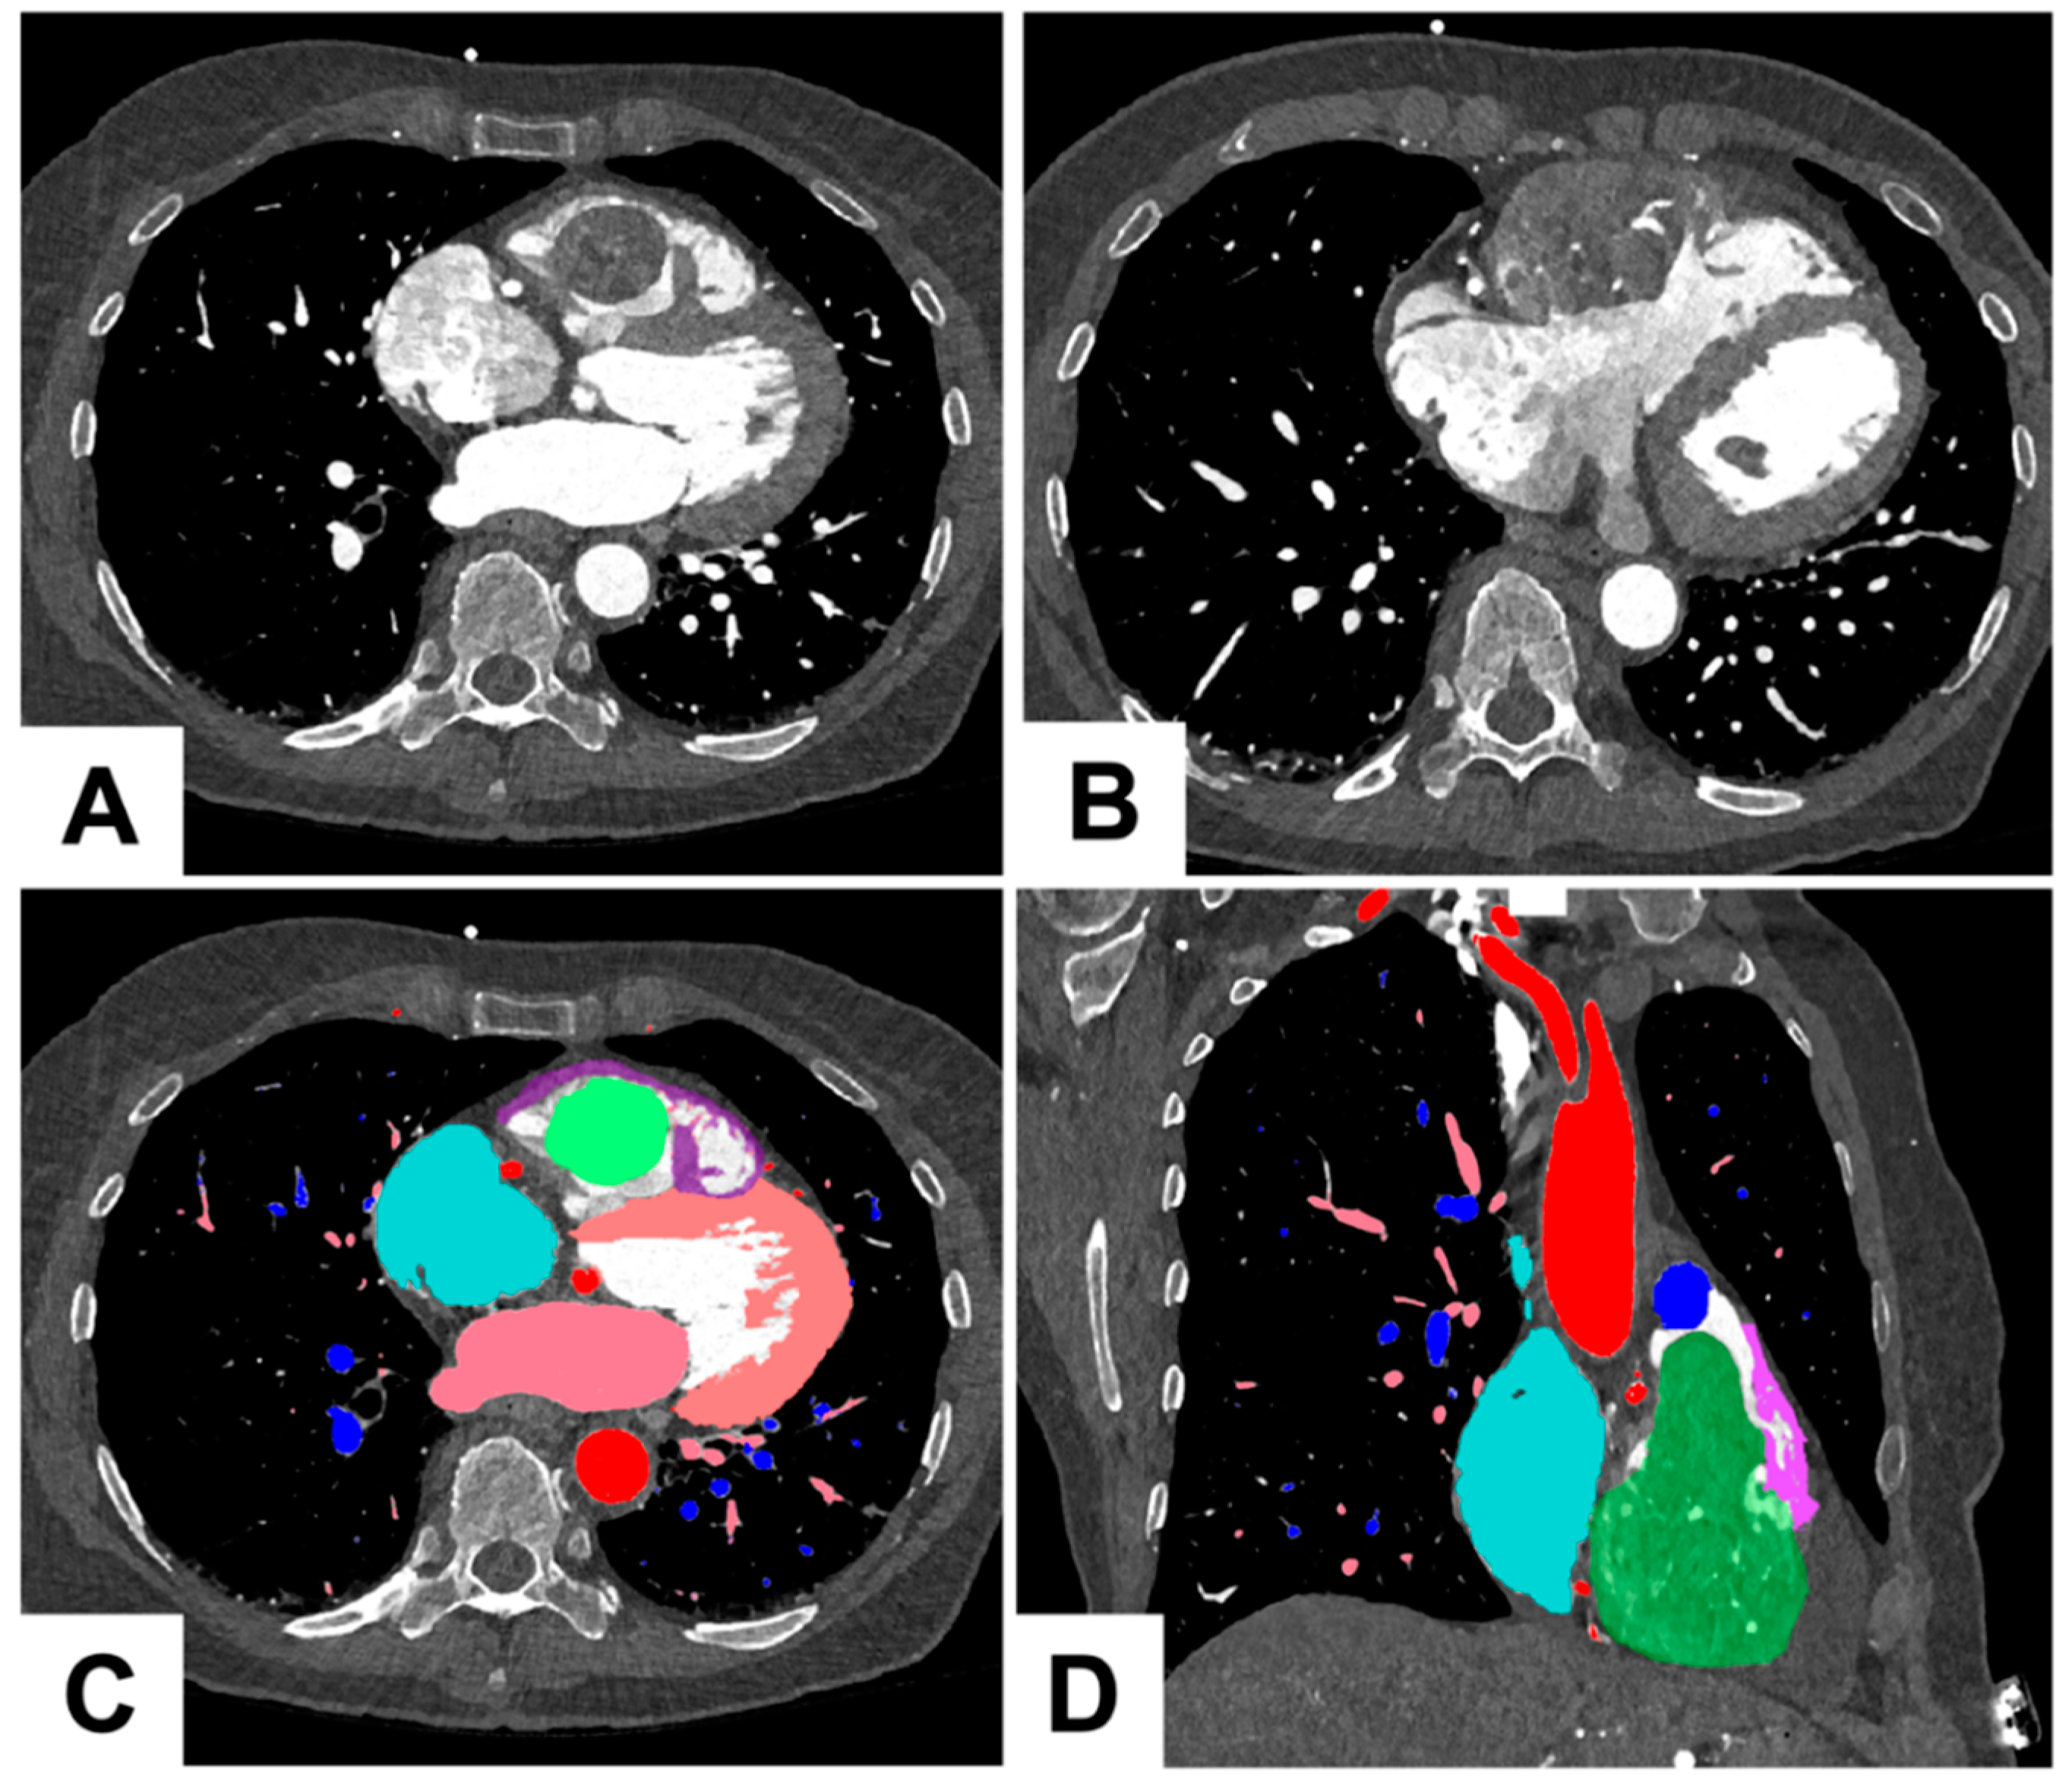

1.2. Three Dimensional Printing Process for the Tumor

As shown in Figure 2 and Figure 3, the 3D printing process for the tumor had several sequential steps. After the imaging process, the 0.2 mm slices were imported into Mimics 24.0 (Materialise, Leuven, Belgium). The segmentation of different anatomical structures was executed through a combination of thresholding and manual segmentation techniques. The segmented structures encompassed the aorta and coronary arteries, blood pools of both the left and right atrium, myocardium of the left and right ventricles, aorta, pulmonary veins, pulmonary arteries, and the tumor itself. The manual segmentation process was a collaborative effort involving an experienced radiologist and a cardiac radiologist working together to ensure accuracy and precision in identifying and delineating these structures.

Figure 2. Illustration of preoperative 3D tumor excision planning. (A) Axial slice: Image illustrating the tumor’s pedunculated section as it approaches the RVOT; (B) Axial slice: Slice demonstrating tumor extending through the myocardium of the RV; (C) Color-coded visualization: The tumor mass is indicated in green, the right ventricle in purple, the LV in peach, the RA in cyan, the left atrium and pulmonary veins in pink, the pulmonary arteries in blue and the aorta in red; (D) Coronal section: The view along the tricuspid plane, displaying the tumor’s pedunculation extending through the RVOT.